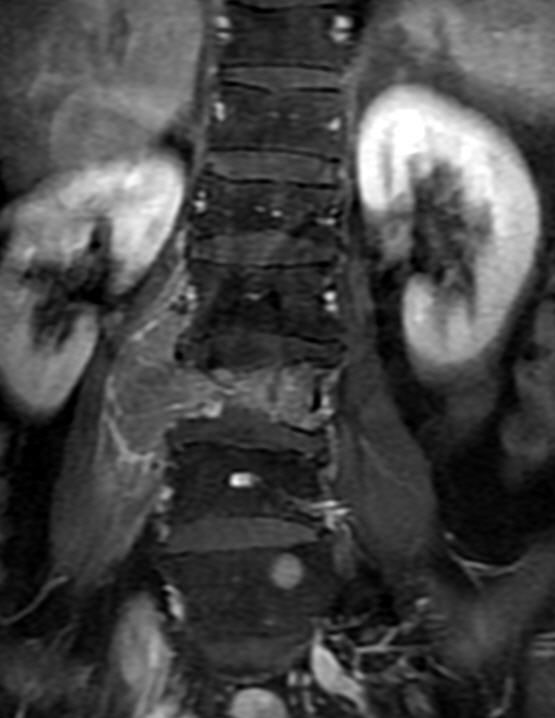

MRI

可提供腰椎管的矢状面、冠状面和轴位横断面上的影像。椎管狭窄以T2加权像显示较好,脑脊液为高信号,产生所谓“脊髓造影”的效果,而骨质增生,骨赘、间盘均为低信号,能清晰地显示椎管狭窄,以及对脊髓的压迫情况。但对肥大的黄韧带、骨质增生等的判断则不如较高清晰度CT扫描。

腰椎正常MRI解剖。

腰椎管狭窄MRI表现。